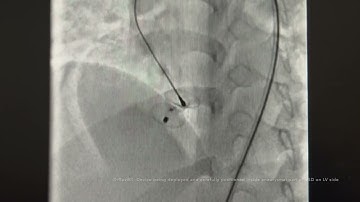

DrRaviRT- Large Post Myocardial Infarction Apical VSD transcatheter device closure